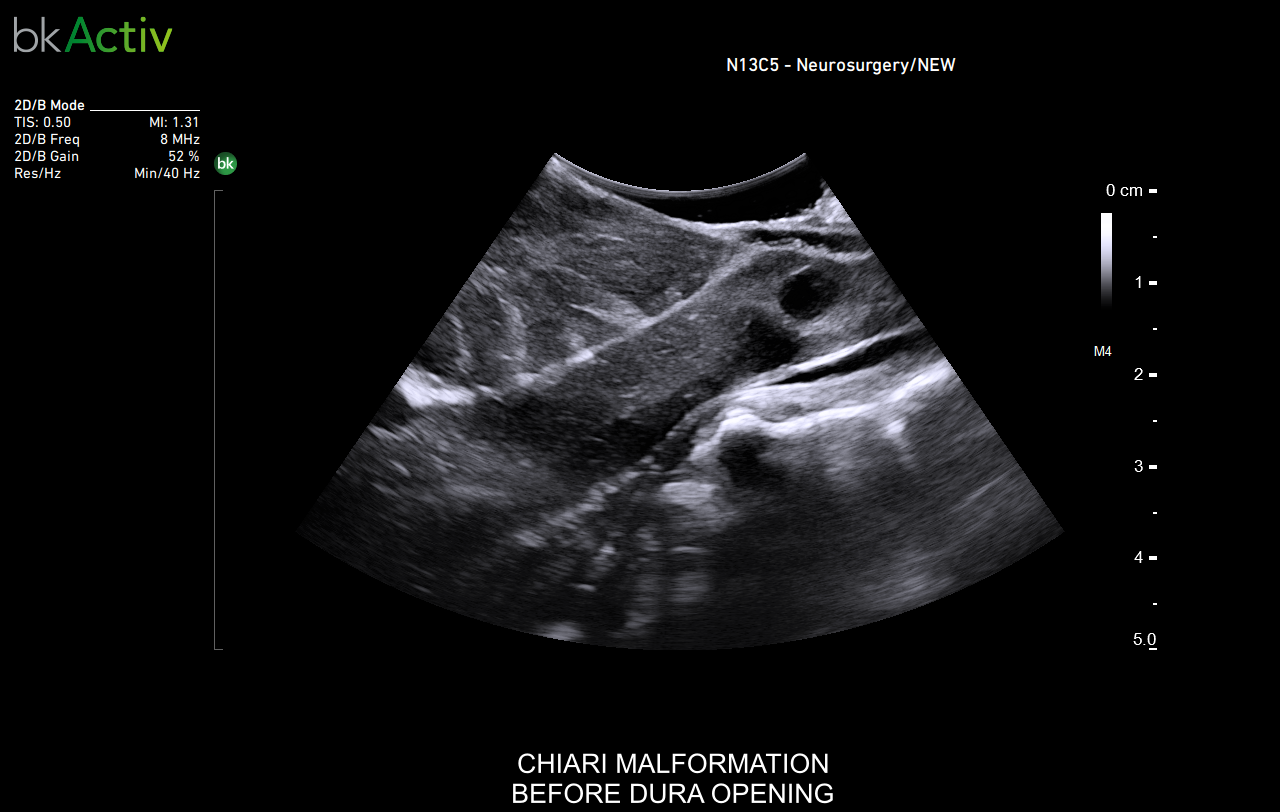

Neurosurgery and Spine

Enhanced Visualization

Improved algorithms that automatically allow uniform image resolution, greater details around lesion borders and at larger depths, and enhanced penetration, spatial resolution, and near field image quality.